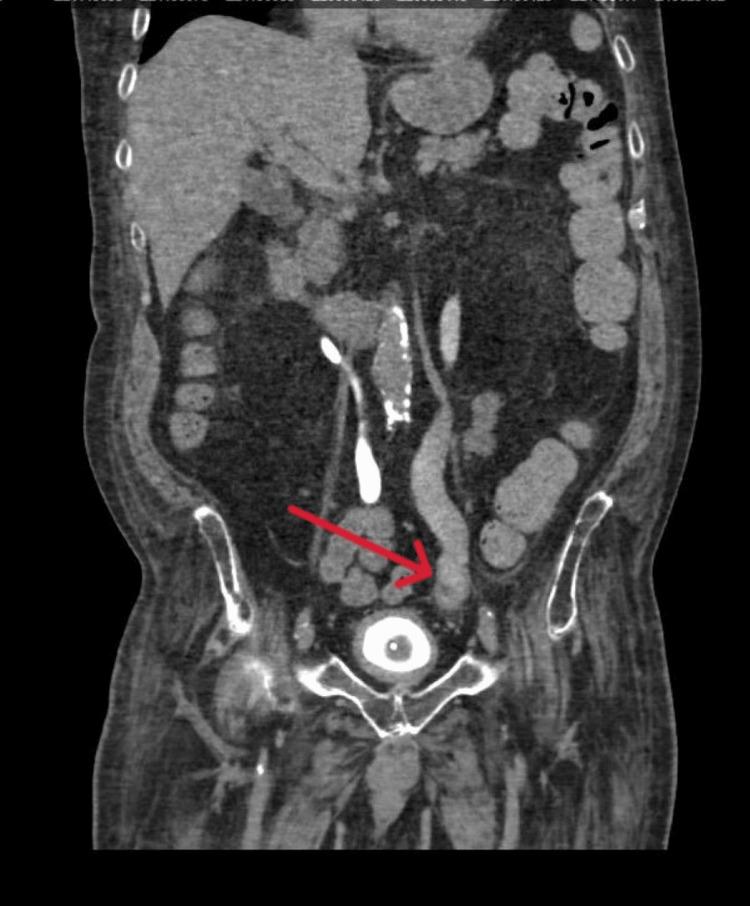

Sodium-glucose Co-transporter-2 Inhibitors Causing Fungemia and Renal Abscess.钠-葡萄糖协同转运蛋白2抑制剂导致真菌血症和肾脓肿

JCEM Case Rep. 2024 Feb 1;2(2):luae010. doi: 10.1210/jcemcr/luae010. eCollection 2024 Feb.